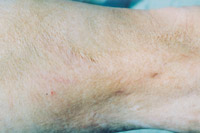

7.浅Ⅲ度创面(右大腿及膝关节表侧)自行愈合后3年,少量瘢痕平坦柔软,无增生,少量色素缺失,皮肤弹性好,不影响职能

201121821471774